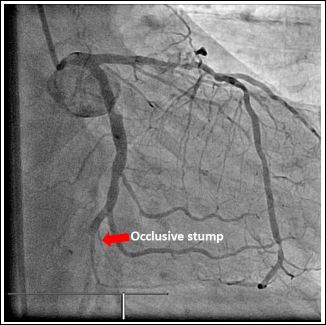

The fourth case was a 51-year-old male known to have hypertension who presented with post exertional syncope. His ECGs showed ST elevation in the inferior leads. He also developed complete heart block and haemodynamic instability. During emergency coronary angiography, multiple attempts to cannulate the Right Coronary Artery (RCA) in its expected location were unsuccessful. Left coronary angiogram with aortogram did not reveal any identifiable RCA origin (Figure 7). There was moderate to severe long segment of disease in the proximal LAD. The Left Circumflex (LCx) artery was a large calibre vessel with an occlusive stump at its distal bifurcation with an obtuse marginal branch (Figure 8). Following wiring of the occluded distal circumflex segment and balloon angioplasty with restoration of antegrade flow, it can then be seen that the Right Coronary Artery (RCA) actually arises from the distal LCx vessel (Figures 9 & 10). After PCI of the distal LCx lesion with a drug eluting stent, patient improved with resolution of bradycardia and hypotension. Patient subsequently made an uneventful recovery.

Figure 8: Left Circumflex (LCx) artery was of a large calibre with an occlusive stump at the distal bifurcation with an obtuse marginal branch in Right Anterior Oblique (RAO) caudal view.